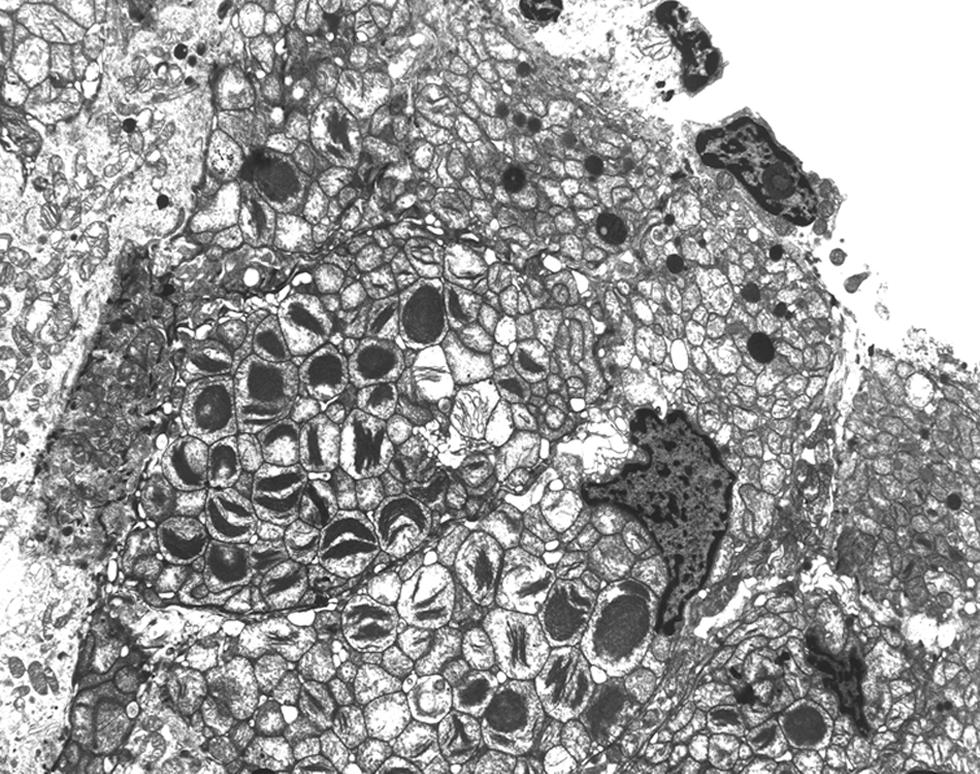

Kearns-Shy syndrome - abnormal mitochondria with paracrystalline inclusions